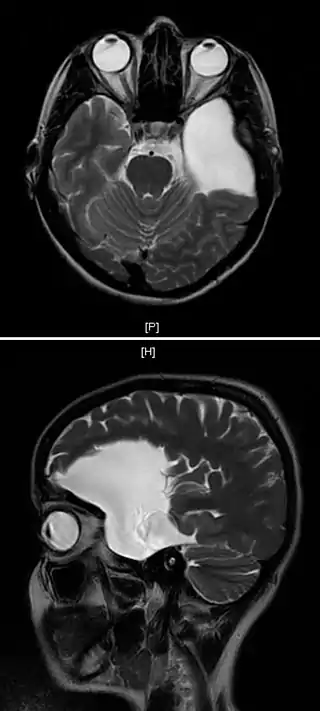

![]() Resonancia magnética de una paciente de 25 años con un quiste aracnoideo frontotemporal izquierdo. | ||

El diagnóstico se realiza principalmente por resonancia magnética. Frecuentemente los quistes se hallan incidentalmente en resonancias magnéticas realizadas por otras razones clínicas. En la práctica, el diagnóstico de quistes aracnoideos sintomáticos requiere la presencia de los síntomas; en muchos casos esto nunca ocurre.